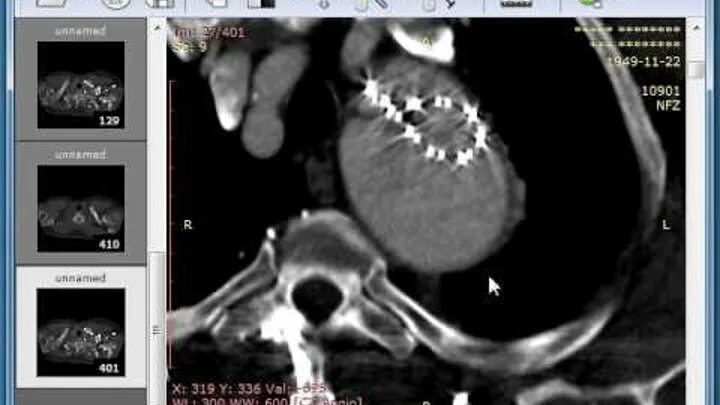

Dicomdir чем открыть снимки мрт